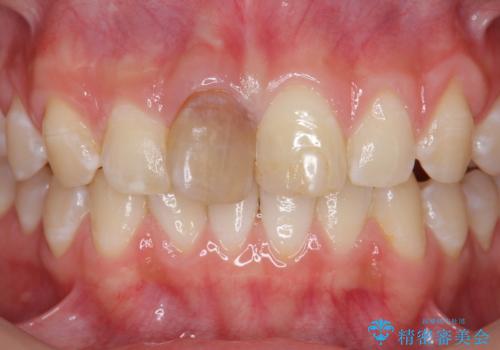

前歯をきれいにしたい ジルコニアクラウンによる審美治療

- 前歯の見た目の改善を求めて来院されました。

ジルコニアクラウンによる審美性の改善を計画します。

失活歯のため捻転を改善し、根管治療は特に希望されなかったのでそのままとしました。

今回失活歯であったため捻転を取り反対側の前歯に揃えて補綴を行うことができました。